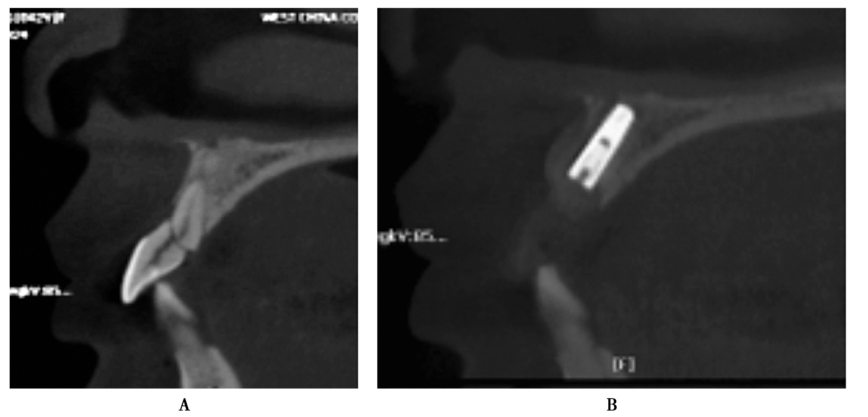

图7 术前矢状位

CBCT片显示牙槽骨密度低,正在愈合中

图9 术前术后矢状位CBCT片

A.牙槽骨密度及高度长度均好;B.显示种植体植入后的位置及高度良好